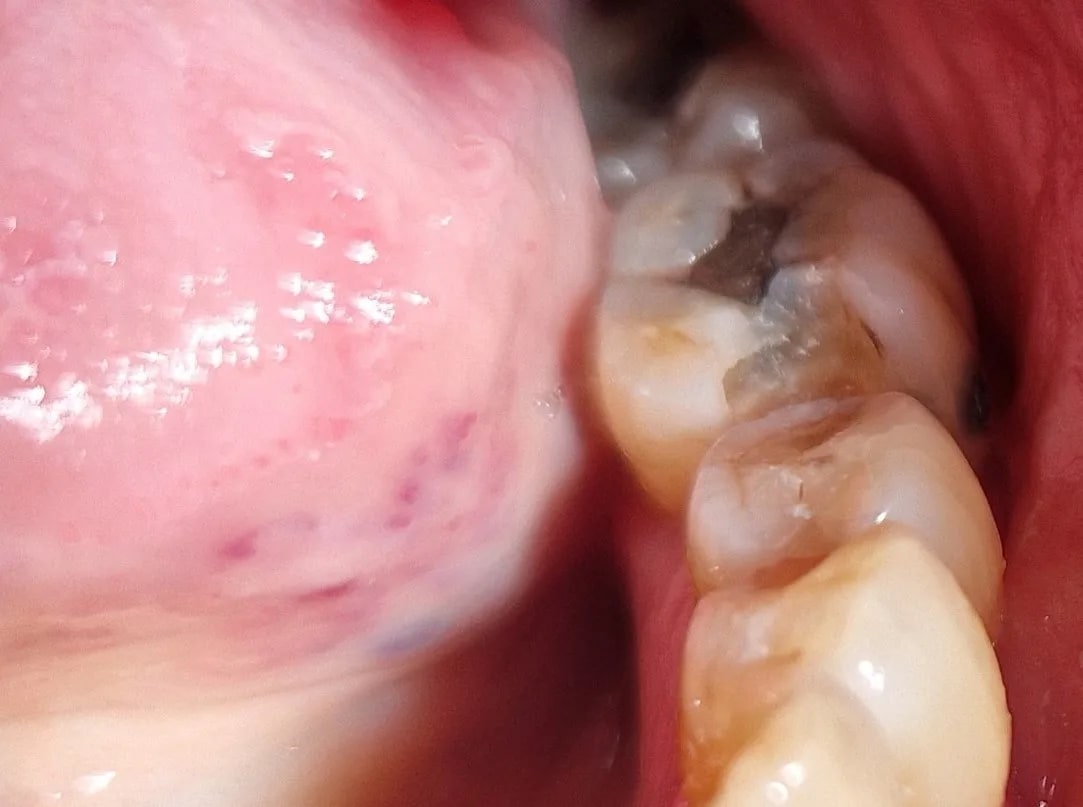

Non mais Dentarue , tu vois sur une photo mer....e qu'il ya une félure ? et tu penses qu' après 35 ans de bons et loyaux services , j'ai déposé un amg et j'ai raté le truc que tu apperçois sur une photo ? non mais faut te calmer un peu ... t'as pas un peu un melon de dinguo ? à coté Raoult c'est une coucourde .... Faut aller faire un tour dans la neige , ça te fera le plus grand bien aux chevilles .

Supprime vite ce vilain trait noir sur la crête marginale distale avec ton blanco, tu mettras tes lunettes la prochaine fois.

C’est peut-être juste une illusion, la faute à polaroid.

Heu dentarue , je vois bien ce trait noir , mais tout ce qui est noir n'est pas une carie ou une fracture .... tu apprendras ça ..ou pas . Mais quand on veut être mauvais , on y arrive facilement .